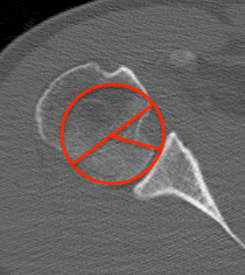

CT scan

Confirms dislocation

Reverse Hill Sachs

Humeral head defect

- caused by impaction of anterior humeral head on posterior glenoid

- intra-articular

- measured as a percentage of the articular surface

Humeral head Defect Management

| Reverse Hills Sachs < 25% | Reverse Hills Sachs 25% - 40% | Reverse Hills Sachs > 40% |

|---|---|---|

|

Non operative Elevate and bone graft if acute Subscapularis / lesser tuberosity transfer |

Subscapularis / lesser tuberosity transfer Osteochondral allograft Hemicap |

Osteochondral allograft Arthroplasty |

|

|

|